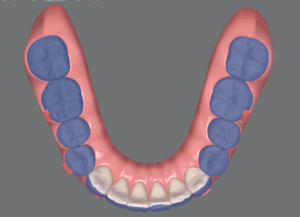

青が追加治療前の状態、白が追加治療後の状態を表しています。

右上2番目の歯を前に出す動きや、下の歯を全体的に寄せる動き、分かりづらいですが上の前歯の傾きを直す動きもしっかり組み込まれています。

ちなみに、11枚のアライナーのうち最後の3枚はオーバーコレクションステージと言って、歯を並べるための移動ではなく、残ってしまったわずかな隙間をキュッと寄せるためのアライナーとなっています。

実際にオーバーコレクションステージを使うとどんな動きをするのでしょうか?

青がNo.8の歯並び、白がNo.11の歯並びです。

上下とも前歯がギュッと下がっていますね。

No.8の時点で余分な隙間がなければ、オーバーコレクションステージは使わなくて良いのですが、通常のアライナーと違いがあるのか気になるので使ってみたいなぁと思っています!